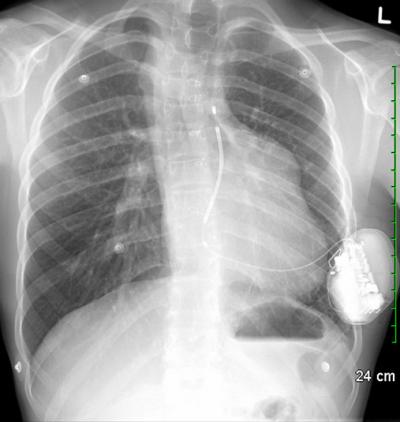

This chest X-ray shows the third subcutaneous implantable cardiac defibrillator (S-ICD) in Canada located under the skin of an 18-year-old patient with congenital heart disease. The electrode can be seen positioned near the heart, but unlike standard ICDs, no part of the device actually touches the heart.

University of Ottawa Heart Institute